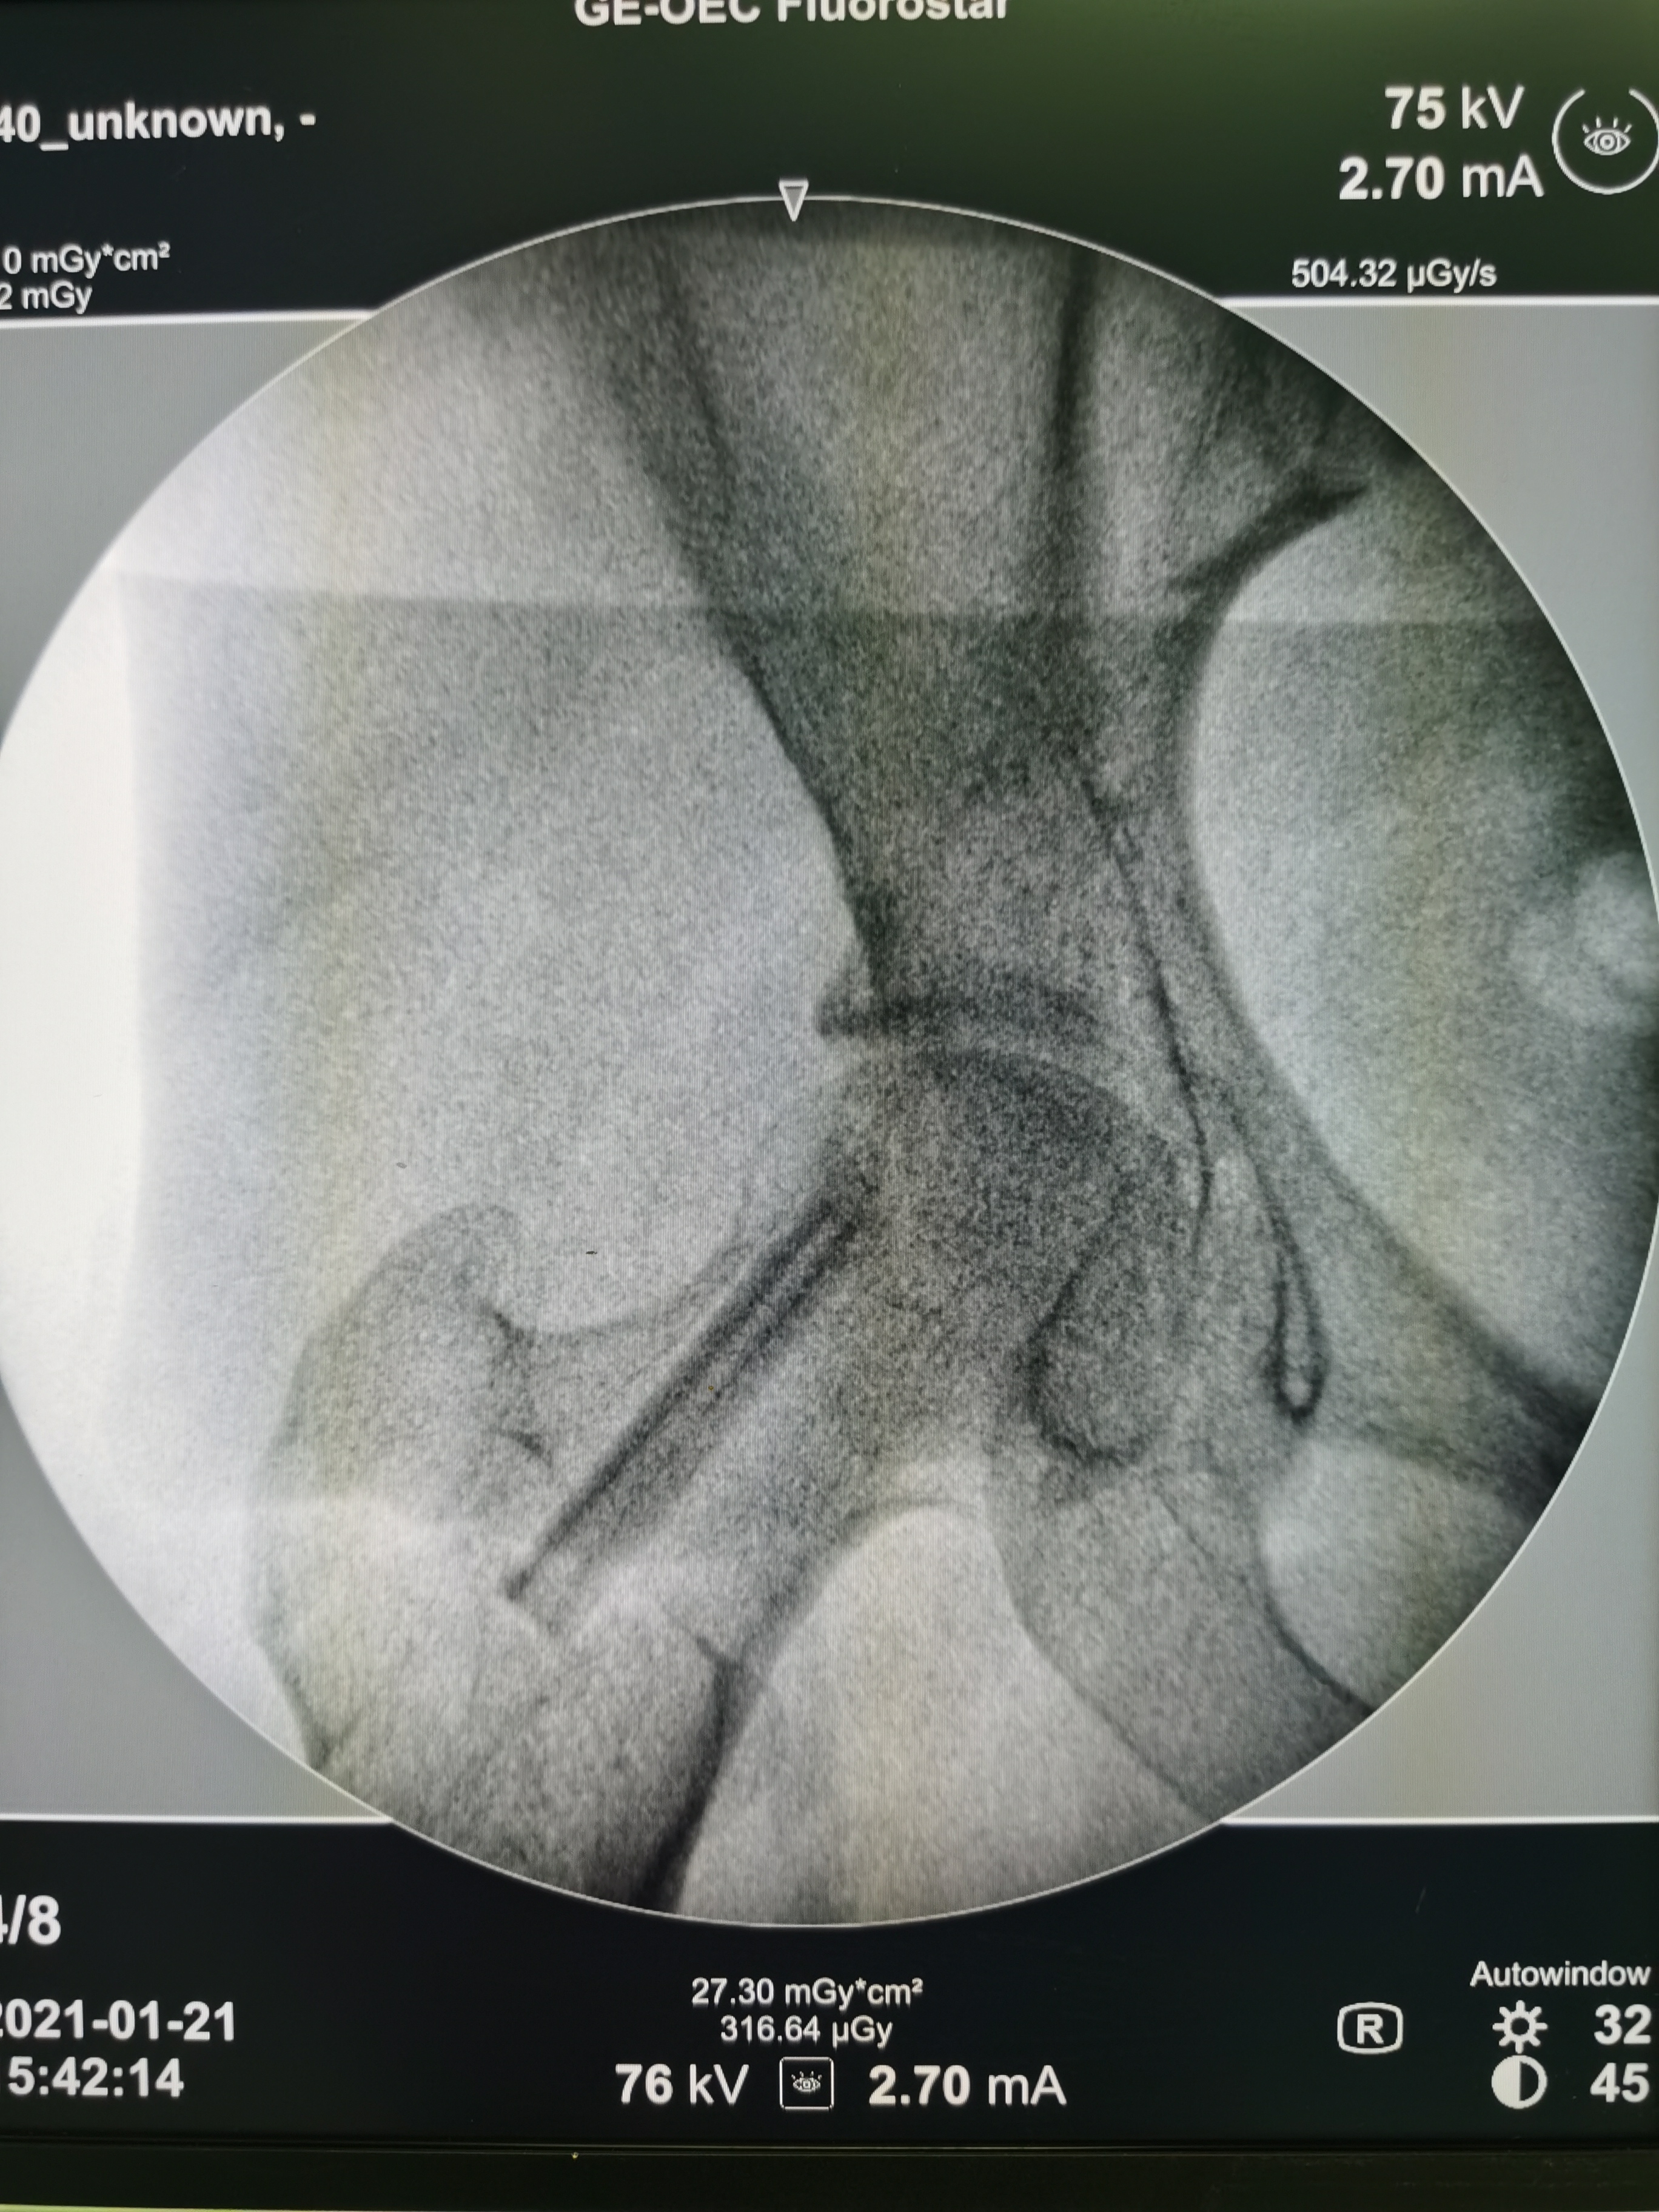

术中,医疗团队在C臂透视下准确定位髋关节,用电动磨钻彻底磨除硬化的坏死骨,然后取用双双自体的松质骨填充到股骨头坏死区,加压填实,保持股骨头的完整性。随后医生从双双的小腿处,截取约5Cm带血管的腓骨,移植到股骨头下,并在显微镜下将直径不足2毫米的动静脉成功吻合,充分保障坏死股骨头的血运,以利于股骨头成活。两侧髋关节的骨移植手术,用时仅3小时。术后,移植骨的血运恢复良好。